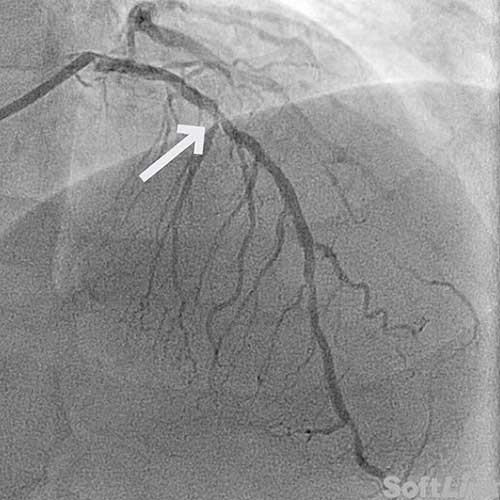

61-year-old male with hypertension, hyperlipidemia, and prior inferolateral STEMI, status post PCI ×2 to the proximal LCx, with residual 70% mid-LAD (D2) disease managed medically.